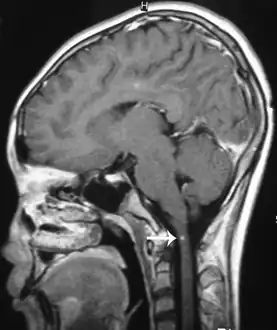

Brain image

Brain lesions, with invasion of brain matter, can be seen on a CT or MRI; however MRI findings may be inconclusive. Sometimes a hemorrhage, probably produced by migrating worms, is present and of diagnostic value.[2][11]